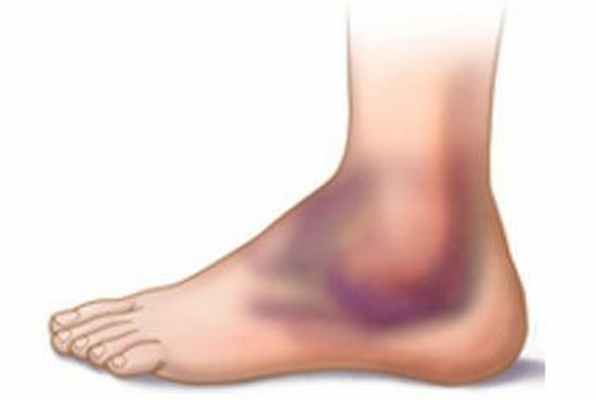

Синяк на коже всегда хорошо заметен. Сначала он имеет багрово-синий цвет, а затем начинает «цвести», приобретает желтую и зеленую окраску. Если под кожей скапливается достаточно большое количество крови, то образуется выступающая шишка. Сначала ее ощупывание очень болезненно, но впоследствии боль проходит.

Сразу после травмы появляется припухлость, а кожа приобретает багрово-синюшный оттенок. Спустя 5 дней кожа приобретает зеленый оттенок, так как распадается гемоглобин. Постепенно гематома рассасывается и «стекает» вниз.